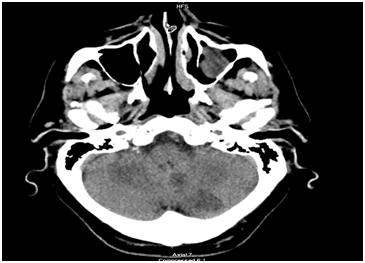

The next morning, the patient was noted to have a change in his neurological exam. He developed dysarthria and ataxia. A stat CT of the head was ordered and showed a new hypodensity within the left cerebellum and chronic periventricular small vessel ischemic changes. An MRI of the brain showed areas of acute infarction in the left parietal lobe, left occipital lobe and left cerebellum with small areas of hemorrhagic transformation in the left parietal lobe infarct. A subsequent MRA of the neck with Intravenous contrast showed a hypointensity in the visualized left subclavian artery which could represent a contrast mixing artifact or thrombus. The stroke was thought to be embolic in nature given the multiple territories involved. Given the MRA findings, a stat CTA of the neck and chest was done for further evaluation. The imaging studies showed the left ICD lead located in the left subclavian artery extending into the aorta and into the left ventricle of the heart. The patient was started on a heparin drip with the plan being to retrieve the ICD lead intraoperatively. Under general anesthesia, the patient underwent a left brachial artery cut down with subsequent removal of the defibrillator generator and lead retraction into the subclavian artery and placing a sheath into the artery. An angiogram was performed which showed that the subclavian artery was patent, and the left internal mammary artery (LIMA) and vertebral arteries were visualized indicating there was no evidence of active extravasation or pseudoaneurysm. In addition, there was no evidence of an arteriovenous (AV) fistula. A new AICD was placed and a subsequent angiogram obtained showed no bleeding. The artery was then repaired with good Doppler signal afterward. The patient was hemodynamically stable throughout the procedure and a post-procedure chest X-ray showed a single lead AICD overlying the right ventricle. The patient’s neurological status improved and the patient was subsequently discharged 2 days later to a rehab facility (Figure 1-3).

Figure 1 CT of the head showing hypodensity within the left cerebellum.